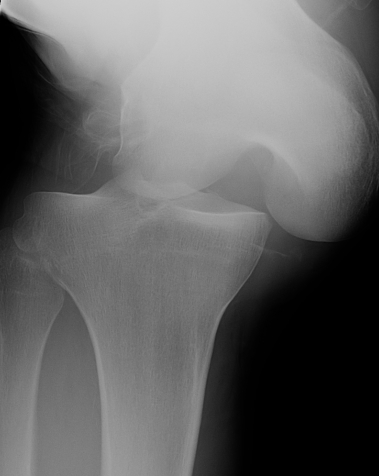

Multi-ligament knee injury (MLKI)

- 2 or more ligaments disrupted

Knee dislocation

- ACL + PCL + one of collaterals

High energy (MVA)

Low energy (sport)

- low energy has 5% arterial injury